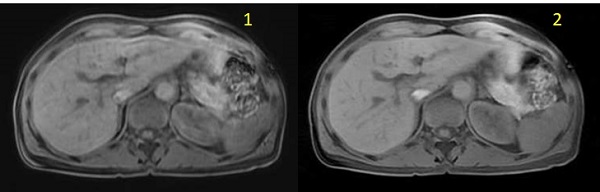

| Number | Description |

|---|---|

| 1 | LAVA free-breathing image |

| 2 | LAVA with Star Imaging Option free-breathing image |